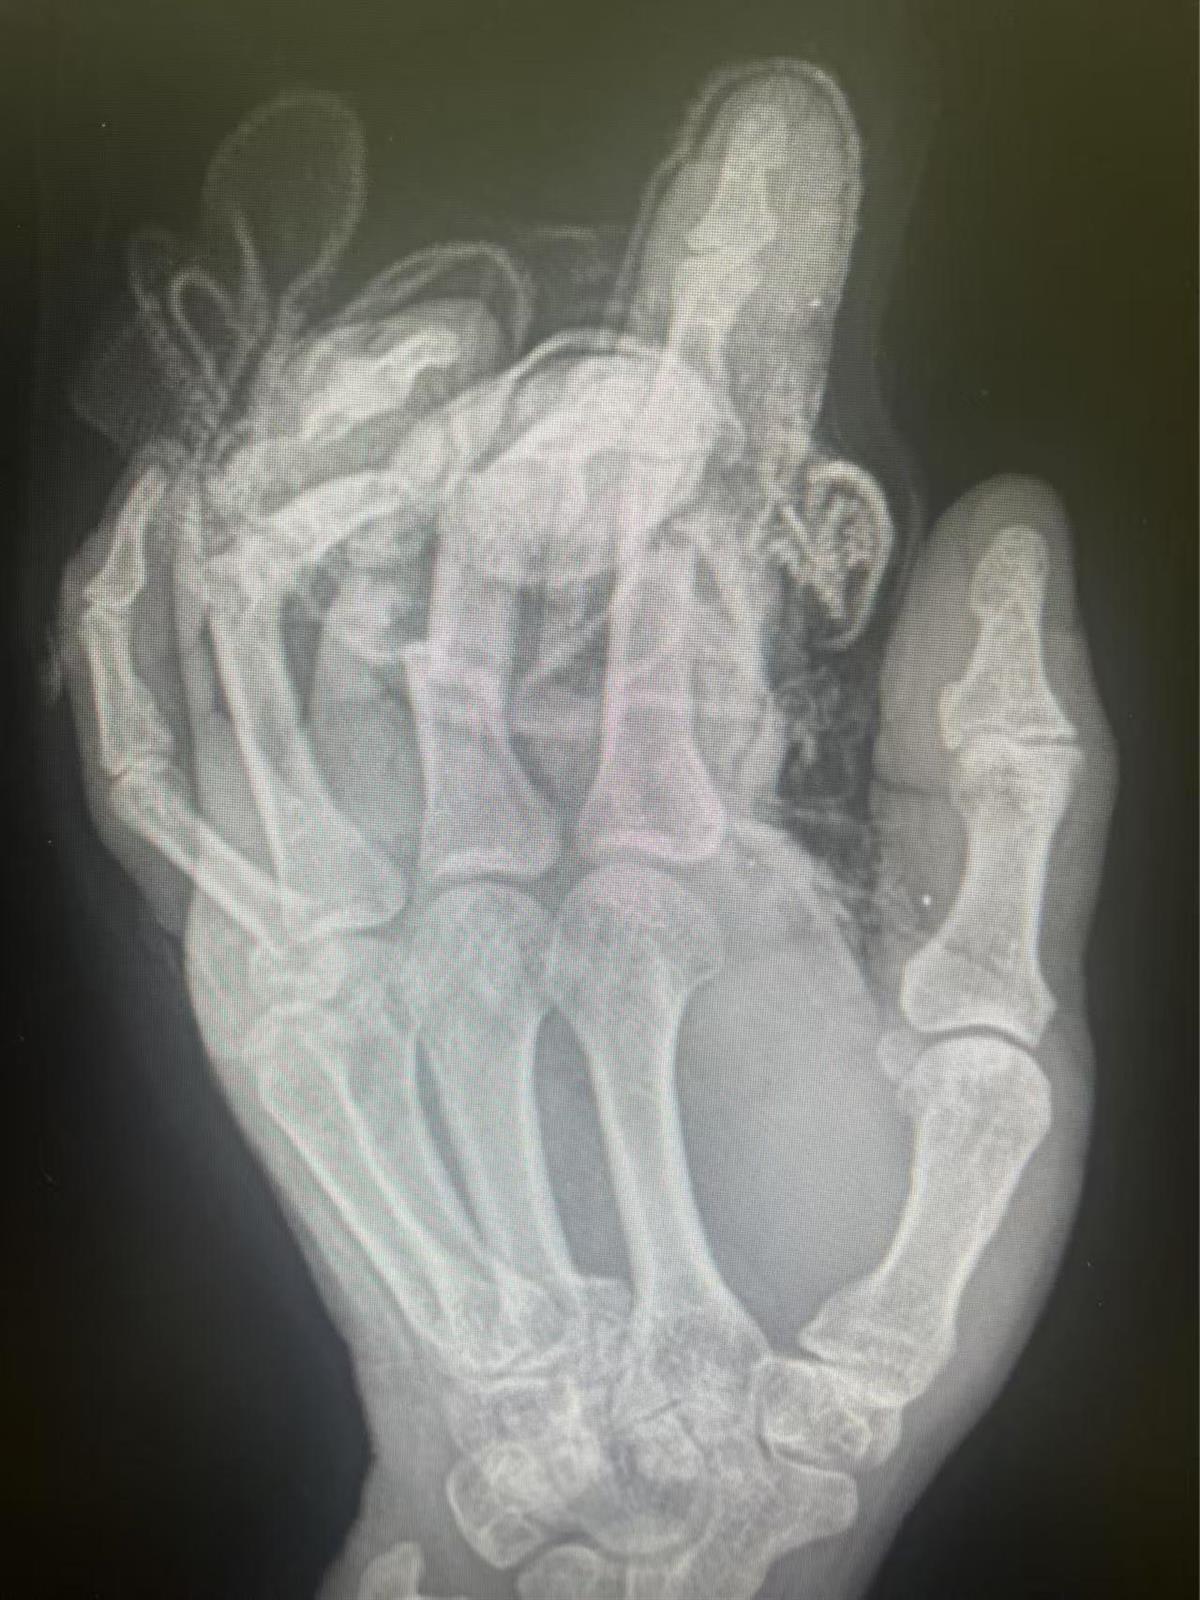

张师傅的手部影像图

13日凌晨一点,47岁的张师傅(化姓)在生产包装盒的工厂内上夜班,一不小心,戴着手套的左手被卷入机器中,抽出时已是血肉模糊,手套连着手被机器绞成了多段。简单包扎后张师傅在工友的陪同下赶往武汉市第四医院。“患者来院时接近凌晨三点,因出血量太大,担心造成出血性休克,一边进行止血处理,一边迅速将患者转到手术室开展再植手术。”接诊的手、显微及修复重建外科中心副主任医师陈焱介绍,患者的左手食中环小指多处指骨开放性粉碎性骨折,血管、神经以及肌腱全部断裂。

“看到患者手指颜色复红后,虽然大家疲惫至极,并且早上马不停蹄的还有专家门诊的出诊任务,但大家仍很欣慰。”手、显微及修复重建外科中心副主任医师陈焱介绍,手术成功只是断指再植成功的第一步,术后若血管循环发生问题,静脉回流不好,仍有可能出现手指坏死,目前患者情况平稳,在经过两周的观察期后才能判定手指是否存活。